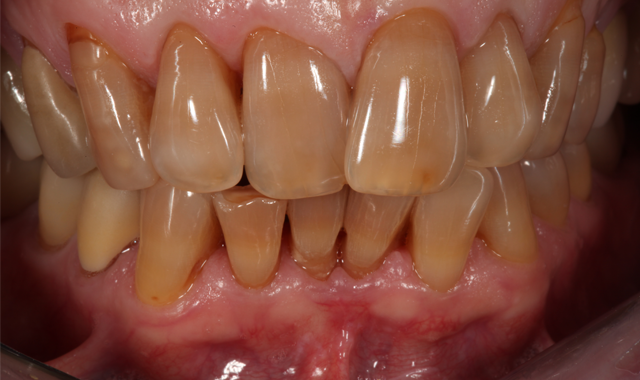

Fig. 1

Fig. 2

A male patient in his mid-60s presented with a chief complaint about the esthetics of his anterior maxillary and mandibular teeth (crowding, severe tetracycline staining) (Figs. 1 and 2). Orthodontic treatment was suggested. However, because the patient had fairly significant sleep apnea requiring nighttime wear of a custom-molded device, he declined this option.